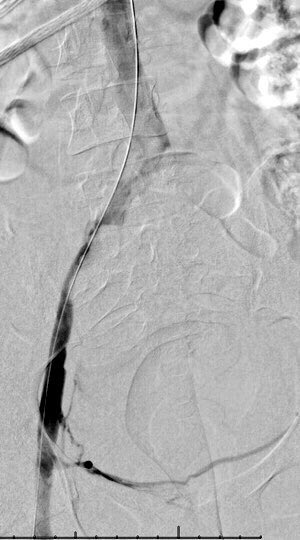

67 yo w/solitary 4cm HCC. Not an operative candidate 2/2 comorbidities and liver function. y90 ablative dose delivered via single arterial supply. Tumor kill dose confirmed with post-y90 PET. albanyir.com/iocase11 #IRad #WithoutAScalpel #IO @SIRRFS @JVIRmedia